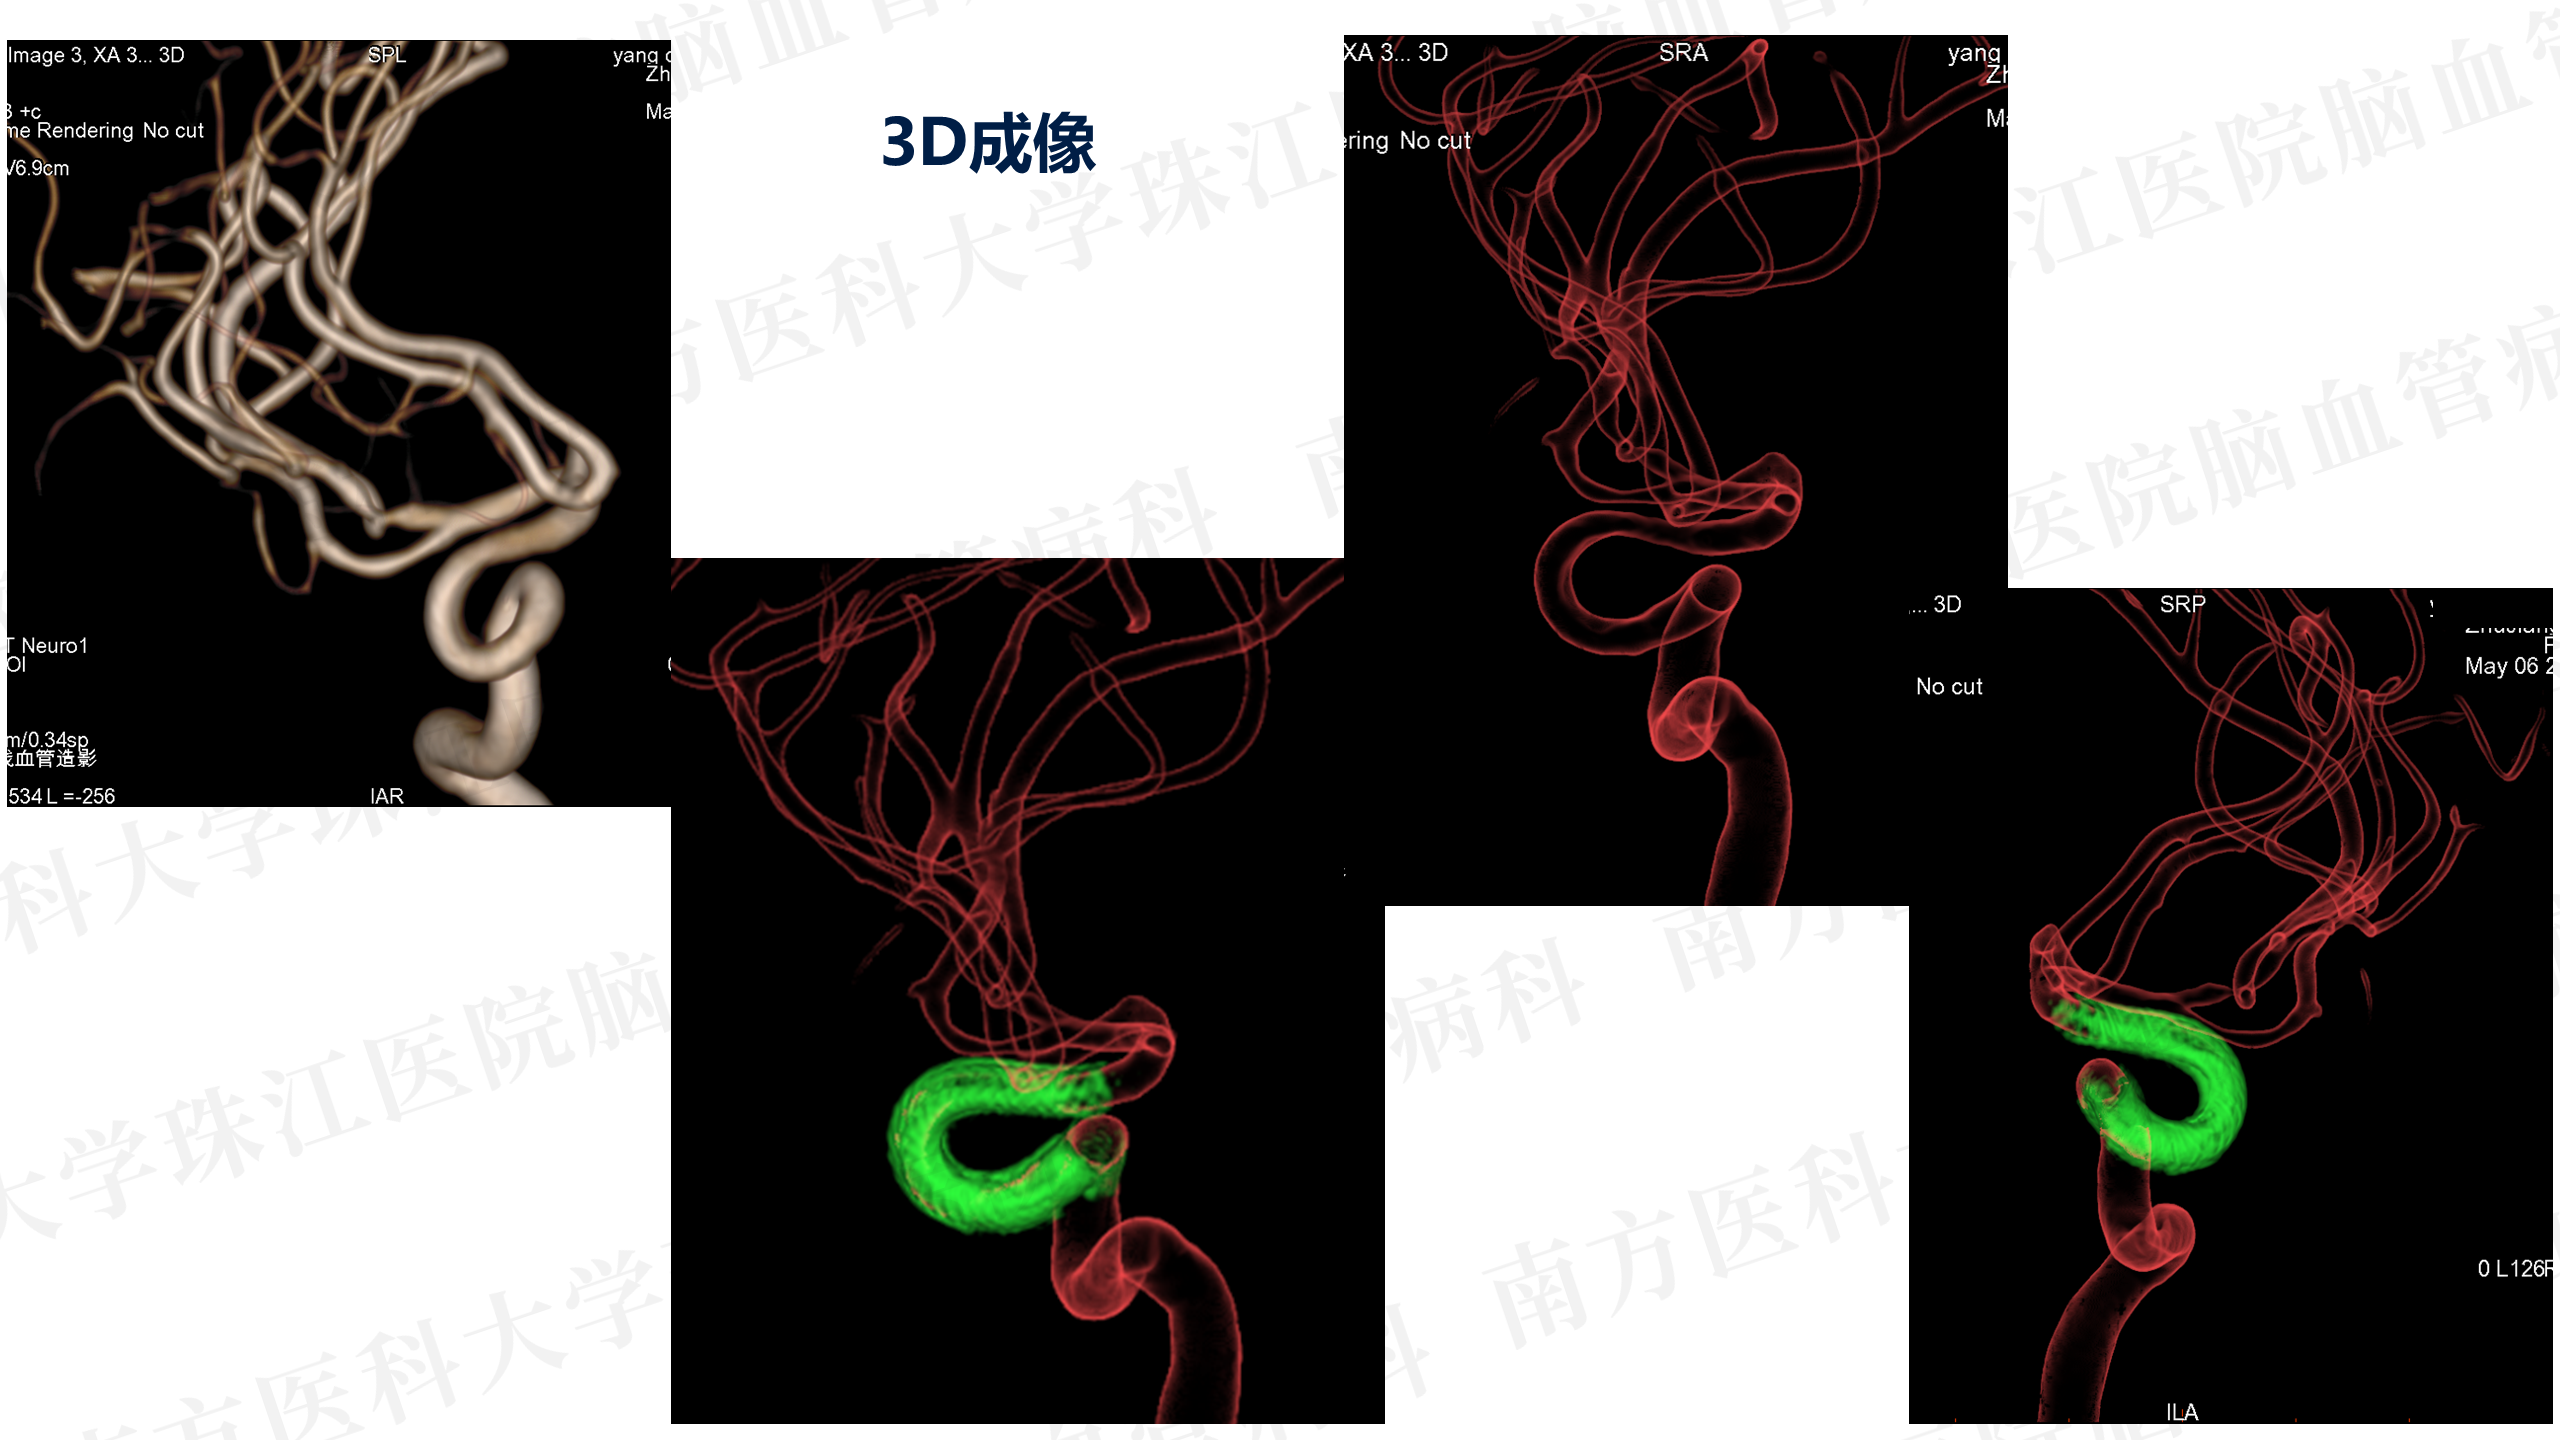

患者入院后造影发现“颈内动脉床突上段巨大动脉瘤,大小约2.7x3.5cm。决定行PIPELINES密网支架植入治疗。

患者入院后造影发现“颈内动脉床突上段巨大动脉瘤,大小约2.7x3.5cm。决定行PIPELINES密网支架植入治疗。